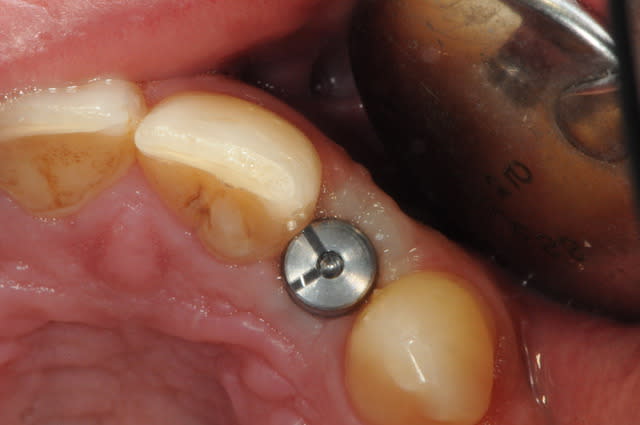

01/09/2010 à 16h28

-cicatrisation de la première vis de cica,

-diamètre plus gros pour la vis de cica

- pilier pour la provisoire

- provisoire moule ION

- ajustage

- polissage soigneux

la suite tout à l'heure, ça sonne à la porte...